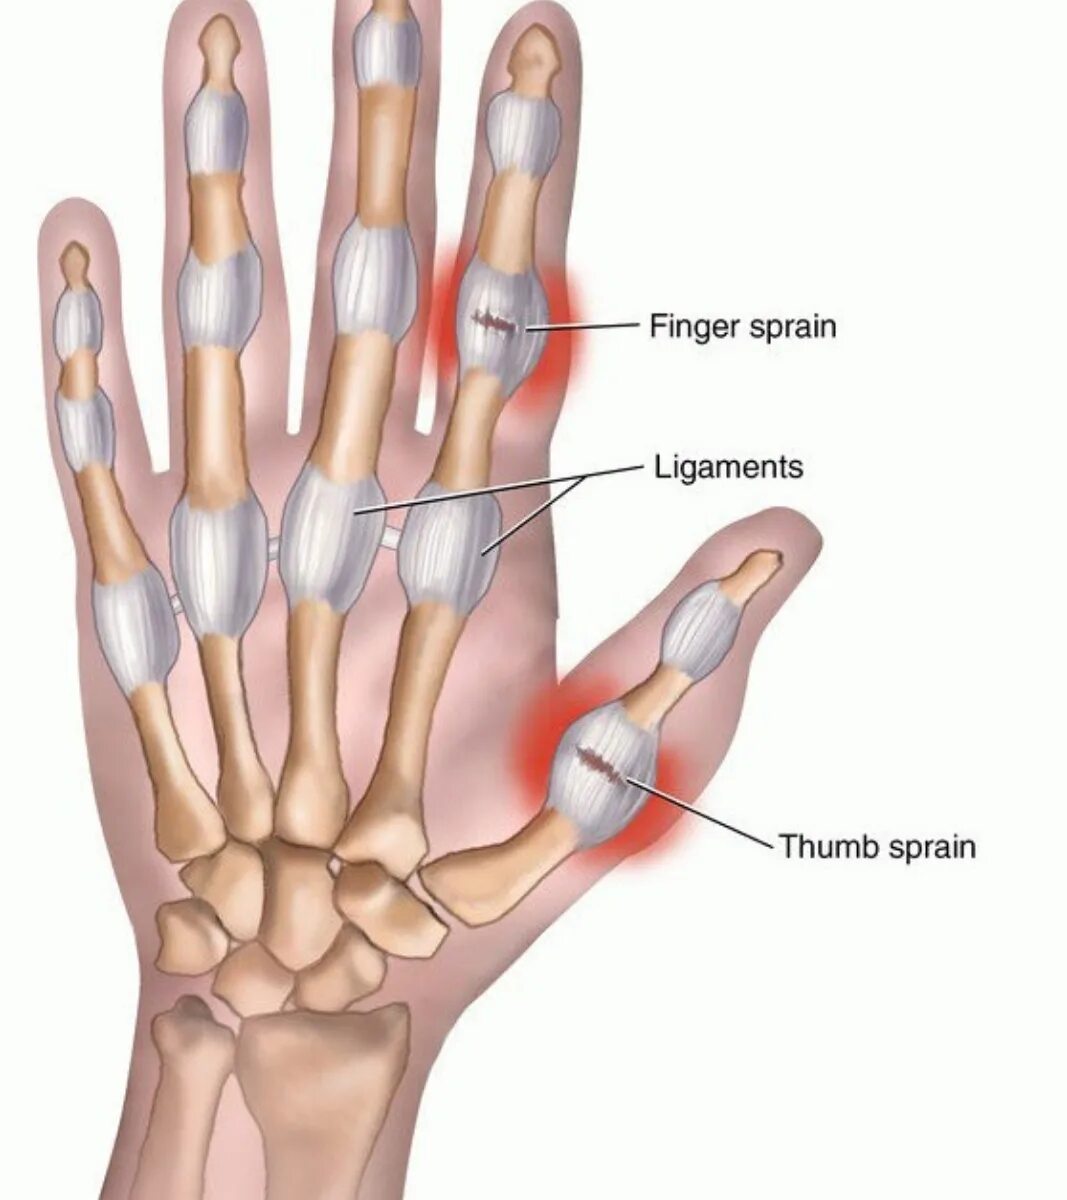

Трубчатые пальцы